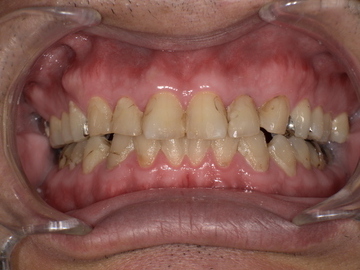

無呼吸症候群のマウスピース装着前

今回ご紹介するのは、耳鼻咽喉科で睡眠時無呼吸症候群と診断され、マウスピースでの治療を希望された40代の男性Aさんの症例です。

<Aさんのご相談内容>

奥様からいびきと無呼吸を指摘された。

朝起きると顎がだるい、寝ても疲れが取れないと感じていた。

日中の眠気がひどく、仕事に集中できない。